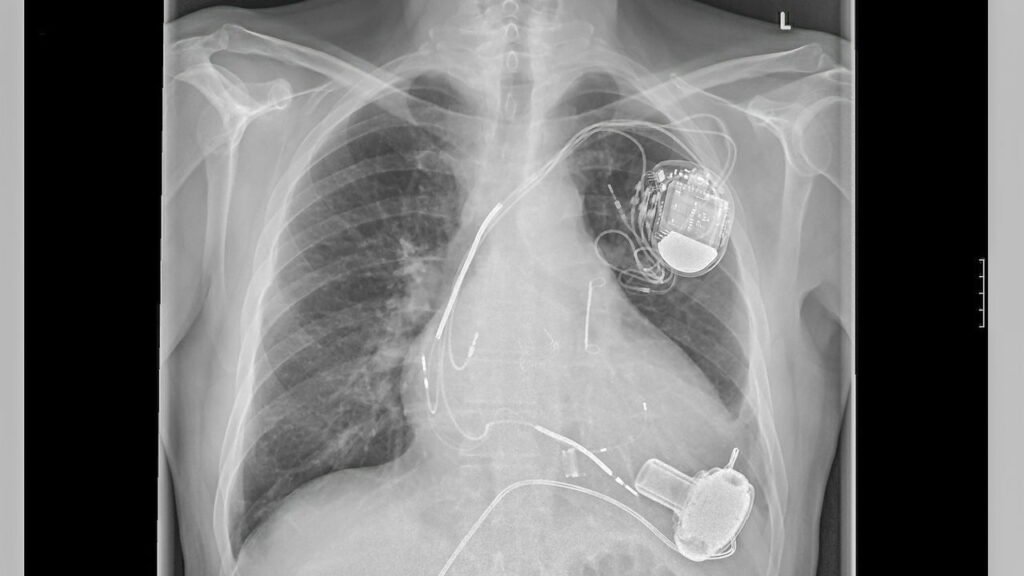

Os Marca-Passos representam uma inovação crucial para a medicina moderna, direcionados ao tratamento de distúrbios cardíacos conhecidos como arritmias. Tais dispositivos são fundamentais para corrigir tanto as taquiarritmias, que são acelerações irregulares do ritmo cardíaco, quanto as bradiarritmias, que causam uma redução no ritmo dos batimentos. Segundo estatísticas recentes, mais de 300 mil pessoas em todo o mundo já possuem o marca-passo, com cerca de 49 mil novos implantes sendo realizados anualmente.